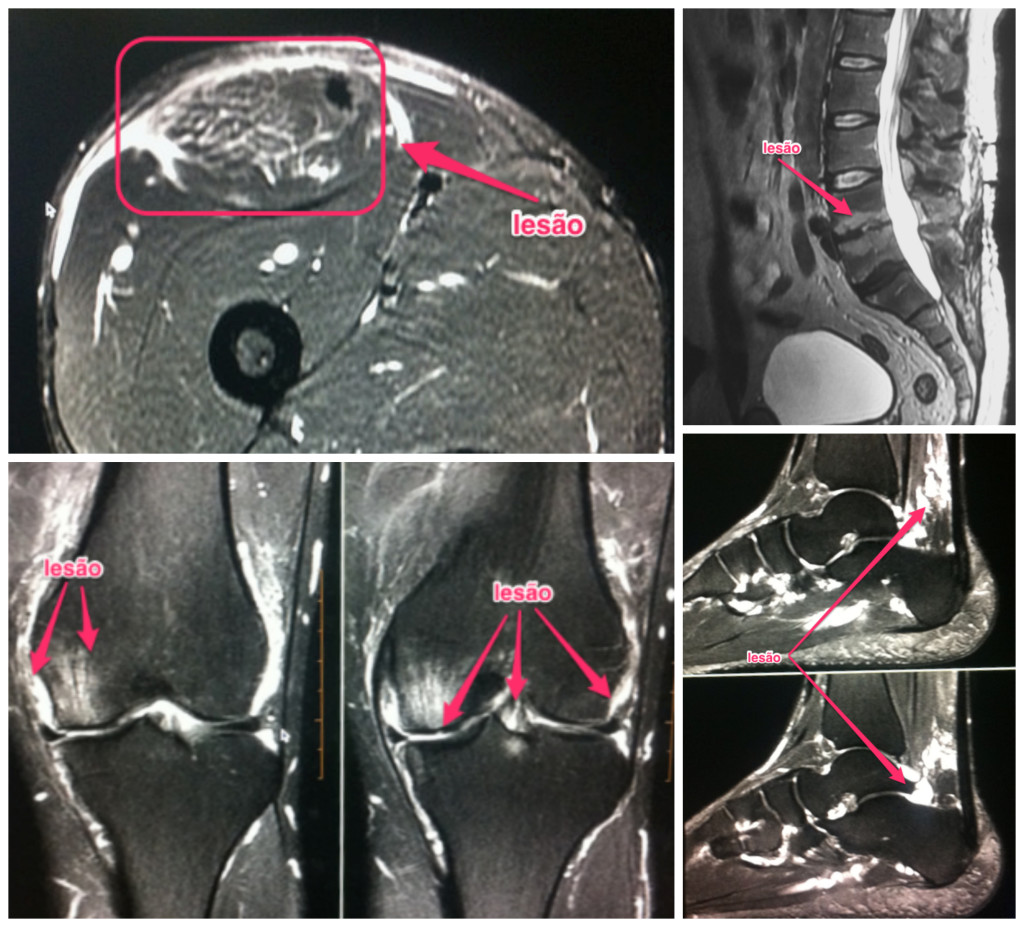

Isso tudo meus queridos amigos, vejo lá no hospital diariamente (atualmente realizo em média 20 exames de RM por dia), vou mostrar algumas imagens.

Essas imagens de RM representam pacientes que exageraram na prática esportiva por má orientação, ou por falta de orientação e acabaram pagando caro por isso.

Quem tá de fora pode achar que estou exagerando, mas na prática o que vejo é muitas pessoas perdendo a oportunidade de continuar a prática de sua atividade física ou esporte e, em muitos casos, a pessoa acaba entrando em quadros de depressão, sobrepeso….enfim.

Isso quando não tem que enfrentar uma cirurgia, que muitas vezes não dá muito certo… acompanho muitos exames pós cirúrgicos e o que vejo às vezes não é nada animador, porém testemunho muitos casos de sucesso.